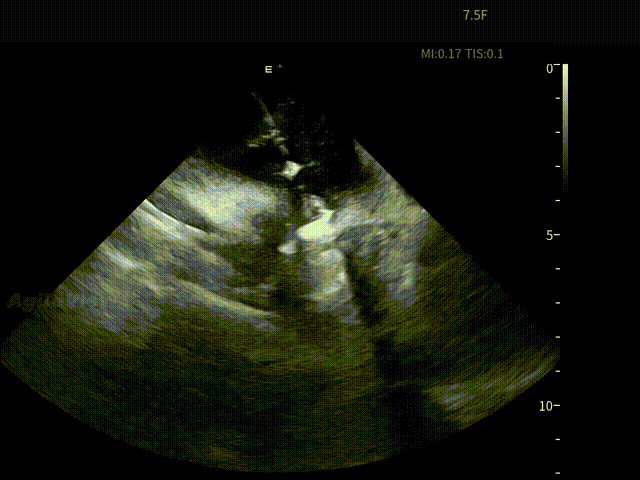

ICE确认LSPV位置——B Mode

ICE确认LSPV位置——C Mode